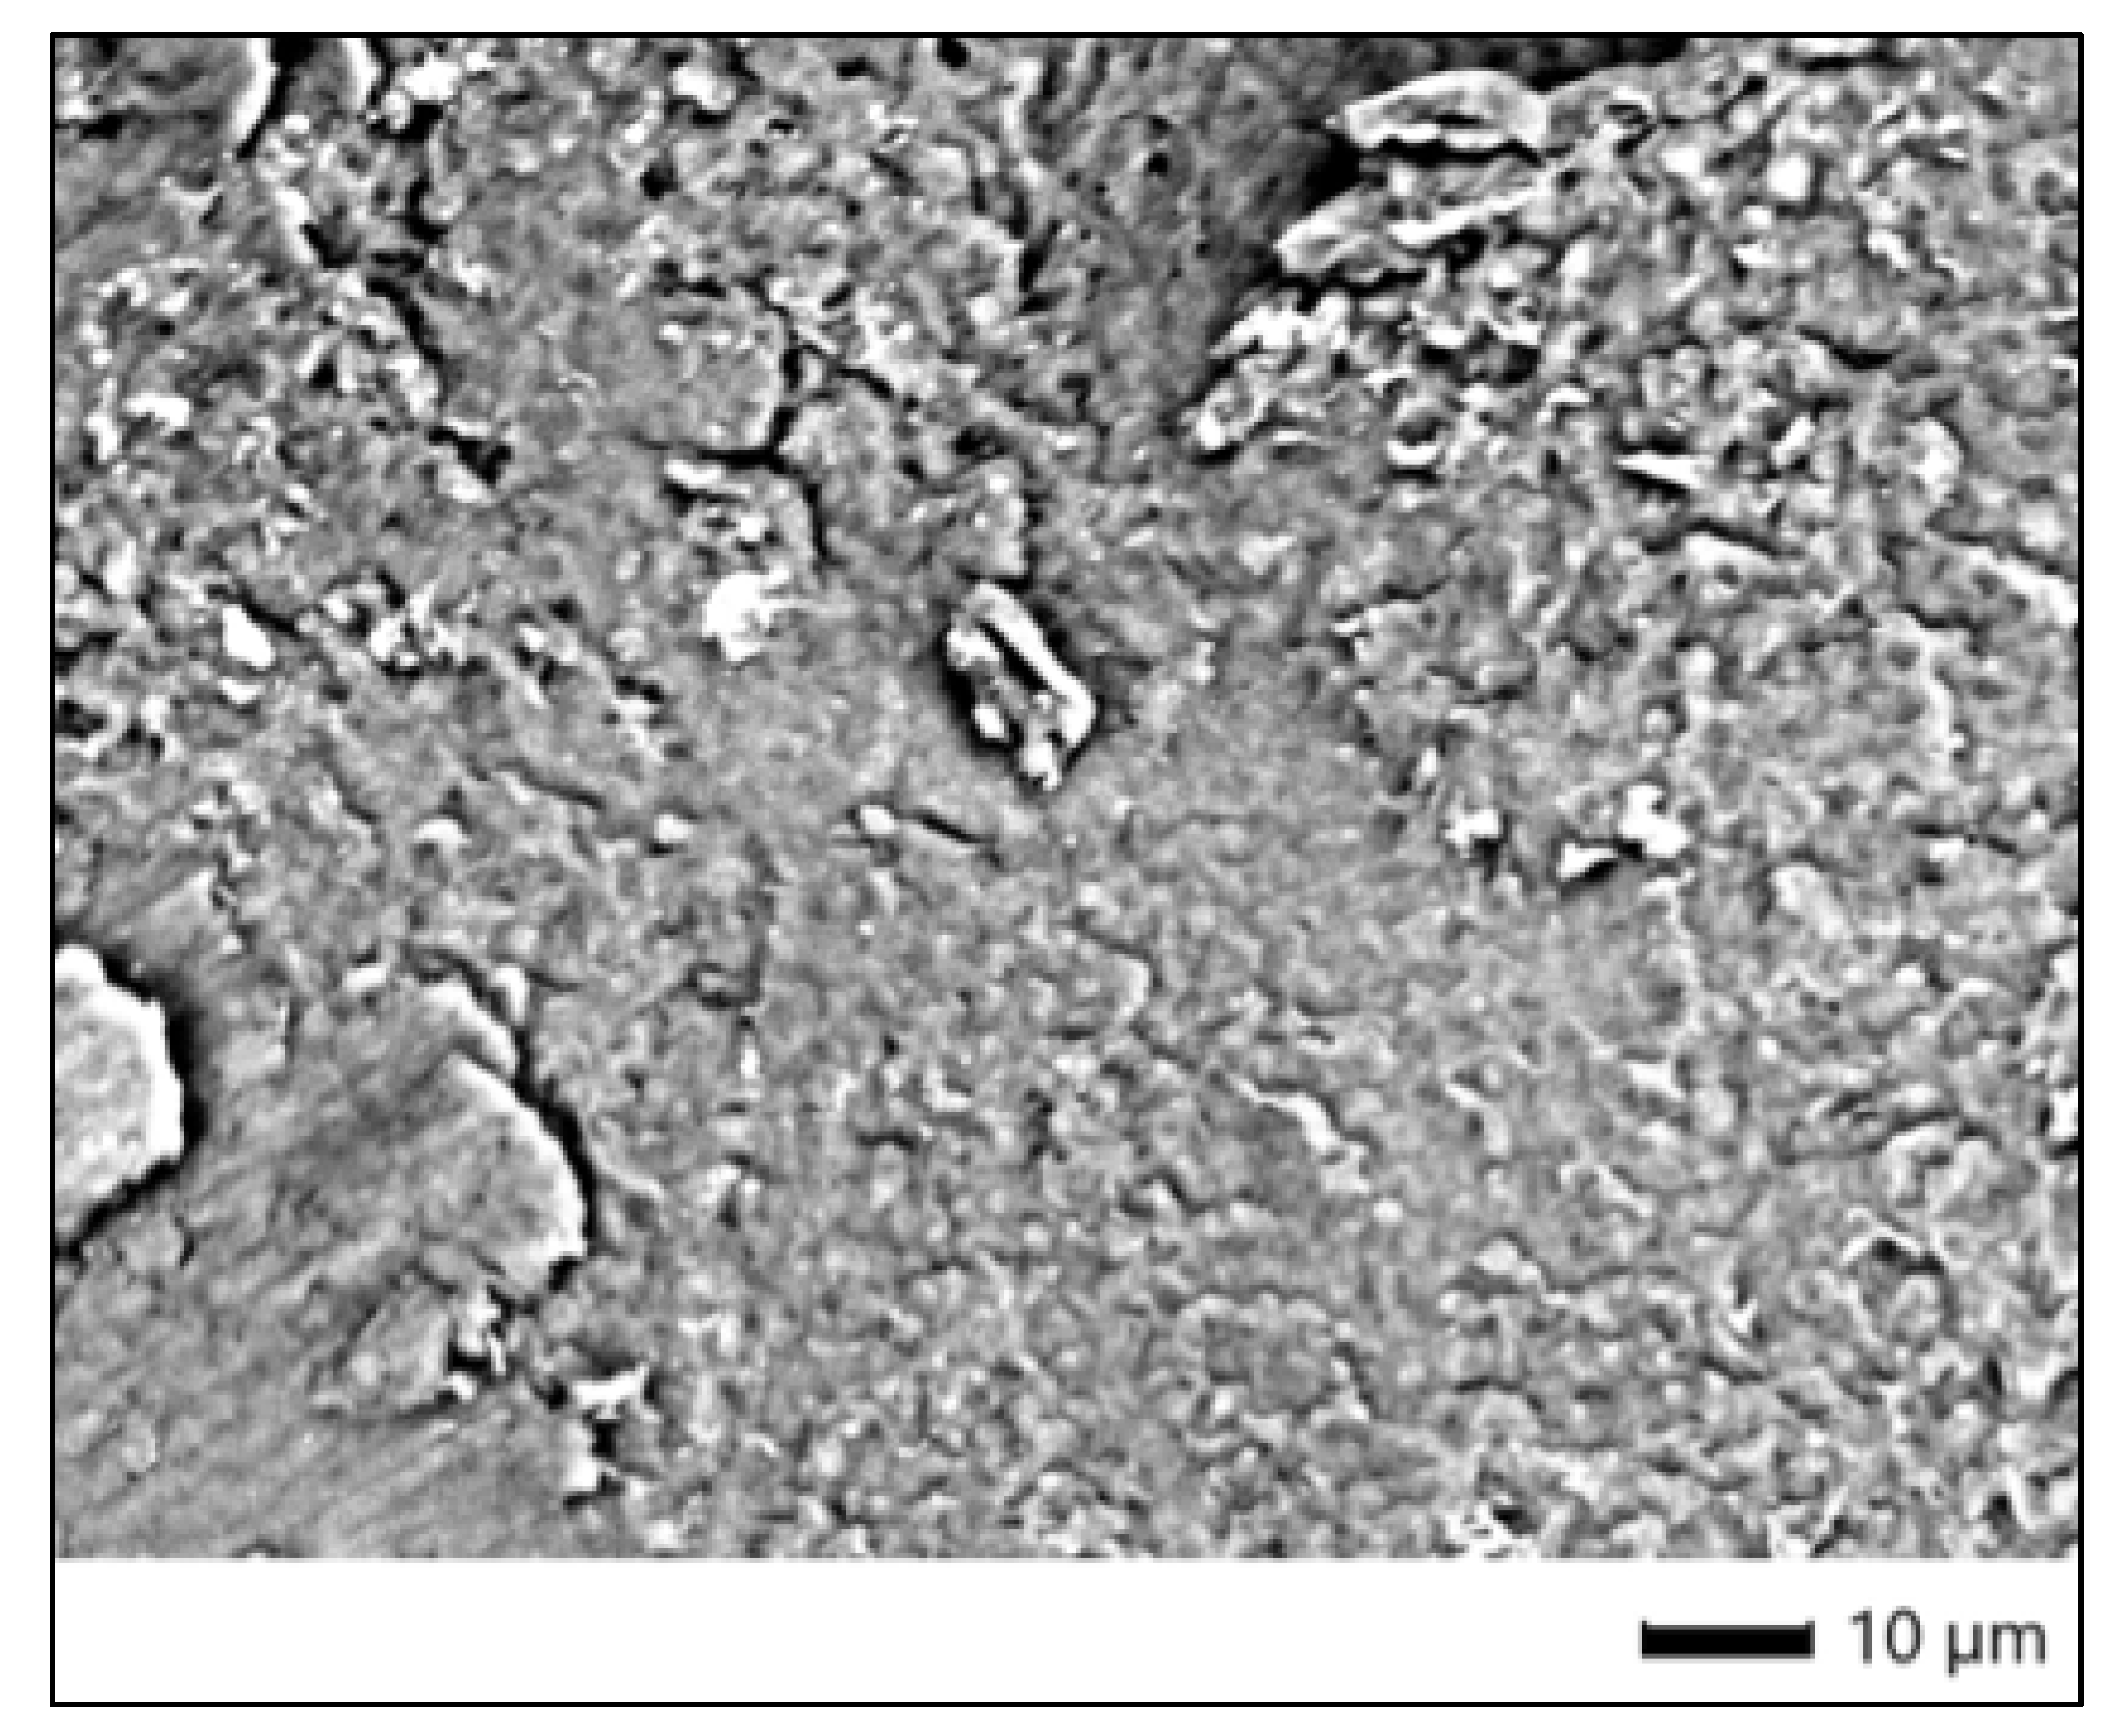

3.5. SEM Morphological Evaluation

The SEM micrograph shows a relatively homogeneous enamel surface with evident polishing striations. There are dispersed particles likely originating from residual debris or environmental contamination, but no significant morphological alterations such as erosion, fissures, or etching are observed. The continuity and compactness of the enamel surface are characteristic of a non-treated control group. This serves as a stable baseline for comparison with bleached samples and confirms the sample’s structural integrity in the absence of oxidative or acidic exposure (Figure 3).

3.6. EDS Elemental Composition of Control Enamel

EDS analysis from the four measured points (Spc_001–Spc_004) indicates a stable and typical elemental composition for sound human enamel. The following elements were detected:

• Oxygen (O): Present in high amounts (31–45%), indicating the predominance of hydroxyapatite and confirming strong mineralization.

• Calcium (Ca): Ranges from approximately 13–28% by mass, consistent with normal enamel mineral content. This is essential for the structural integrity of enamel.

• Phosphorus (P): Detected at 7–15%, aligning well with stoichiometric expectations for hydroxyapatite (Ca10(PO4)6(OH)2).

• Carbon (C): Measured between ~15–25%, potentially due to the presence of organic components or superficial environmental carbon residues.

• Sodium (Na): Found in trace levels (~0.5–1.1%), which is typical for enamel and may influence its solubility.

• Magnesium (Mg): Minor quantities (~0.3–0.7%), known to substitute for calcium in enamel apatite and slightly affect its properties.

• Chlorine (Cl): Present at low levels (~0.2–0.3%), likely surface contamination.

• Silicon (Si) and Aluminum (Al): Detected only in one region (Spc_004), suggesting possible extrinsic contamination or sample holder residue.

The relatively low standard deviations and consistent Ca/P ratios across spectra confirm that the enamel chemistry is intact and unmodified, which reinforces the validity of this sample as a proper control reference in bleaching studies.